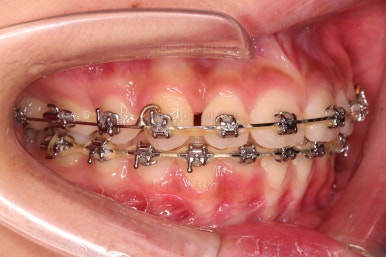

위아래 치열이 매우 고르게 되었으며, 이제부터는 발치공간을 줄여나가면서 교합을 맞춰 나가면 됩니다.

이번 환자분 같이 편악발치의 경우에는 윗니에만 발치 공간이 있고, 치아 사이즈의 부조화가 생겨서 발치 공간이 남거나 다 모아놔도 추후 재발이 되는 경우가 많습니다.

굉장히 디테일한 치료계획과 수행이 중요합니다.

이번 환자분도 다양한 테크닉으로 편악발치이지만 공간이 잘 줄어들 수 있게끔 치료해 나갑니다.

입매, 웃을 때의 입술선과 치열의 조화 등을 체크해줍니다.

디테일한 마무리를 하고 종료합니다.